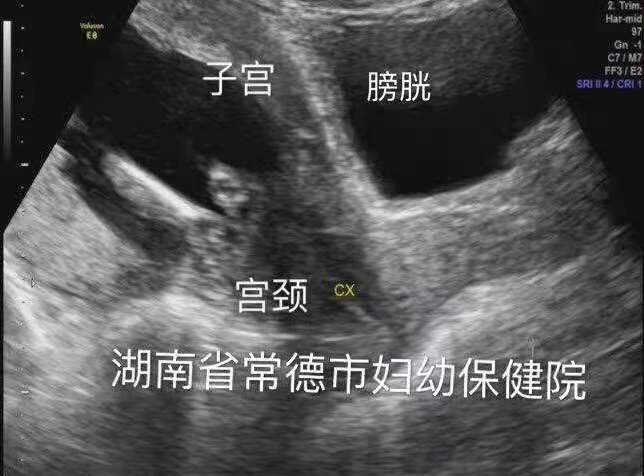

尿潴留缓解,子宫位置已转前位,宫颈远离尿道